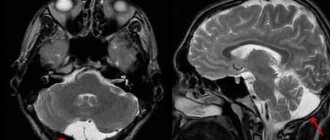

Ретроцеребеллярная арахноидальная киста

Ретроцеребеллярная киста формируется при смещении сосудистого сплетения четвертого желудочка вверх и назад от интактного червеобразного отдела мозжечка. Для выявления такого типа кист приблизительно одинаково информативными являются КТ и МРТ.